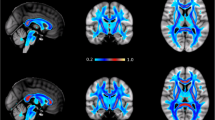

Fifty-one non-operated sCS patients with a median age of 0.40 [IQR 0.25] years were included, which involved Apert (n = 8), Crouzon-Pfeiffer (n = 14), Muenke (n = 8), and Saethre-Chotzen (n = 10) syndromes, and complex craniosynostosis (n = 11). Seventeen control subjects were included with a median age of 1.20 [IQR 0.85] years (Table 1). The measured tracts are visualized in Fig. 1.

The summary shape of the tensors of each voxel in a 3D ellipsoid is shown in Fig. 2 with the mean ʎ1, ʎ2, and ʎ3 of patients and controls for the corpus callosum genu and hippocampal segment of the left cingulate bundle. We see the three major, medium, and minor axis of the diffusion displacement. Both two ellipsoids show any degree of anisotropy or orientation in 3D space. The control group shows smaller ellipsoids in comparison with sCS patients. The corpus callosum shows a more anisotropic ellipsoid than the cingulate bundle, which has a more Gaussian appearance.